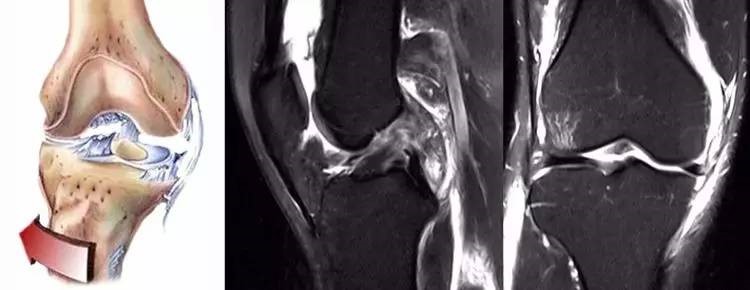

ACL损伤的间接征象:指ACL断裂后胫骨前移位出现的一系列改变。间接征象只能考虑可能有ACL损伤。

1.骨挫伤(轴移征):一旦ACL撕裂,胫骨就相对于股骨前移,使股骨外侧髁和胫骨外后方撞击,双方均出现水肿,而且膝关节屈曲的程度决定股骨髁挫伤的部位。

14.jpg

2.沟槽征:当股骨外髁骨因撞击造成的凹陷深度>2mm时称为沟槽征,代表受到撞击的暴力更大。

15.jpg